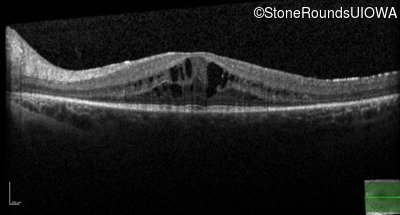

Optical Coherence Tomography - Right - 20/32 -1

Exemplar / OCT Stack

OCT Stack